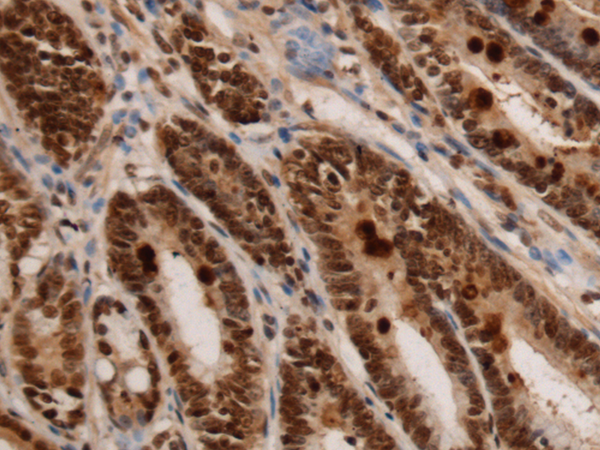

IHC positive control: |

Human colorectal cancer and Human gastric cancer |

IHC Recommend dilution: |

150-300 |